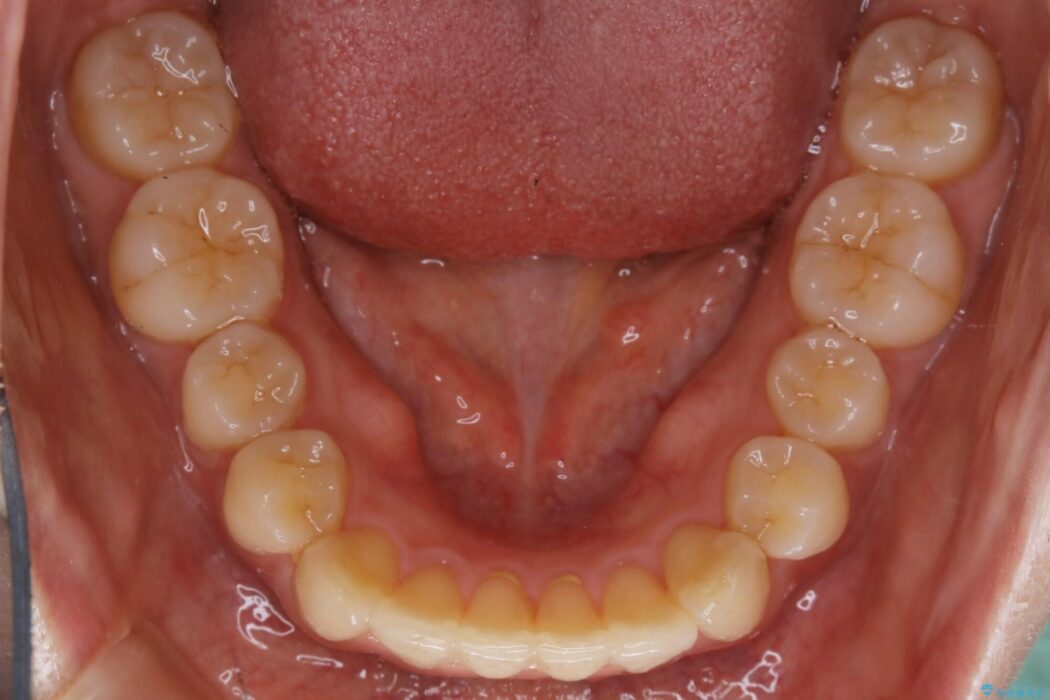

下額前歯が少しガタついていることを気にされて来院されました。

検査をしたところ奥歯の噛み合わせなどに問題が見られなかったため、軽度のねじれがある下顎前歯に焦点を当てた部分矯正の適応が可能と判断し、インビザラインのライトパッケージをご提案しました。

本症例では奥歯に関して問題がほぼ見られなかったため、部分矯正を行うことが可能と判断しました。

通常の全体矯正と比べピンポイントの部分矯正となると、動かす歯が少なくなるため治療期間が格段に短くなり、費用が抑えられることがメリットとして挙げられます。